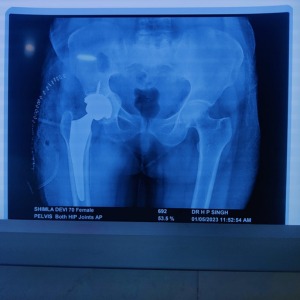

HIP REPLACEMENT

Hip replacement is a surgical process to replace the damaged bone and cartilage with prosthetic components. Jyraj Clinic is the leading multi-specialty clinic having immense experience in performing hip replacement surgeries.